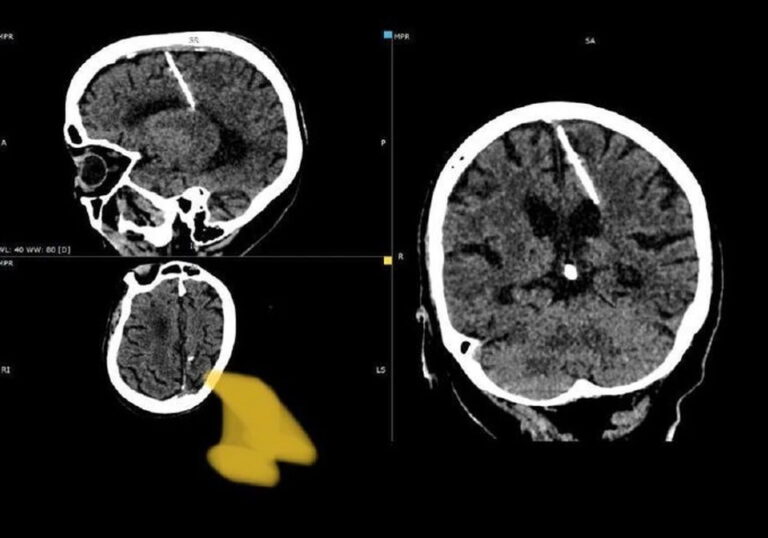

Фото: Минздрав Сахалинской области

На Сахалине рентгенологи столкнулись с необычным случаем – у 80-летней пациентки они обнаружили трёхсантиметровую иглу в мозге. Женщина даже не подозревала, что у неё в голове есть инородное тело, сообщает в телеграм-канале Минздрав Сахалинской области .

Девочке повезло – игла проникла в левую теменную долю мозга, но она выжила. При этом головные боли пациентку никогда не беспокоили. Иглу обнаружили только в этом году при проведении компьютерной томографии.